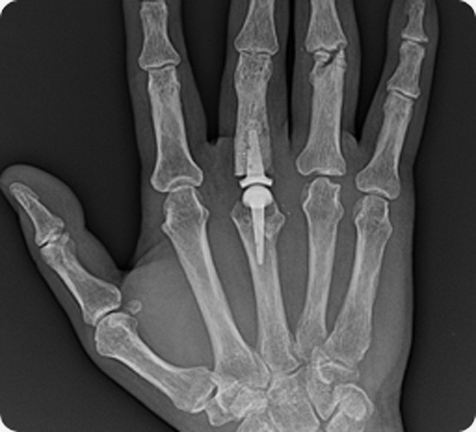

단순 방사선 사진과 초음파 검사를 통해 수술의 가능 여부를 확인하는 것이 중요하다. 이런 인공관절은

1960년대 후반부터 실리콘을 이용한 손가락 인공관절이 유행되었으나 파손, 파모, 탈구, 염증 등 문제가

생겨났고 손가락 운동능력이나 손가락 모양이 완전히 회복되지 않아 불편했다.

인체 뼈조직에 잘 접촉해 시멘트 없이도 고정시킬 수 있고 마모율이 적어 한번 시술하면

반영구적으로 사용할 수 있으며, 기존 실리콘 재질에 비해 더 큰 운동 범위와 강한 힘을

갖는 것 또한 장점이다. 수술은 간단하지만 적절한 환자를 선택하는 문제와 의사의 손수술에

대한 기술력이 좋은 결과를 위해 반드시 필요하다. 손안에는 여러 마디가 있는데 그 중 3,4번째

중수지 관절이 손 인공관절에 가장 좋은 적응이 된다.